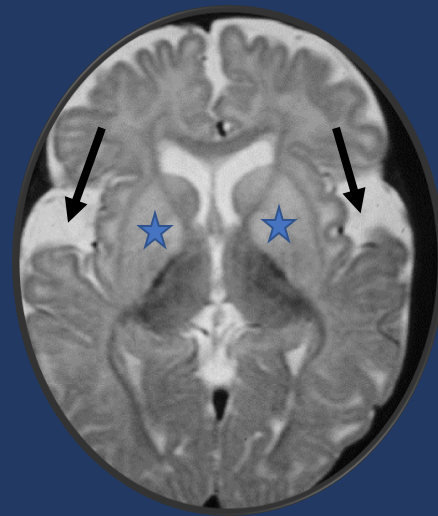

Tip of the day 💡: Not many causes of a large head a leukodystrophy! Once you pick up signal changes in the basal ganglia and the open opercula (arrows), you have clinched the diagnosis of Glutaric Aciduria Type 1. Do you know which other leukodystrophies accompany large heads?